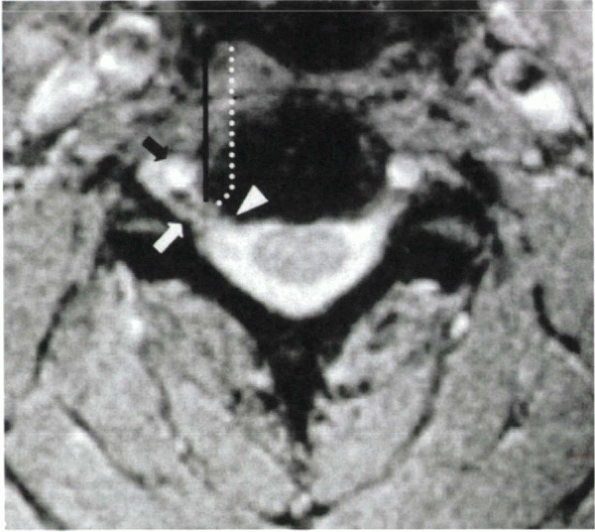

Figure 26-1 (A)

Large posterolateral disc herniation. The disc compresses the thecal sac and the exiting nerve root. A disc in this location would be difficult to access safely from a posterior approach. (B) Foraminal disc herniation, left side. (C) Uncinate hypertrophy. The uncinate spurs arise from the superior and the inferior vertebral bodies at C3-4 and C4-5, leading to foraminal narrowing (black arrows). This is a common mechanism for foraminal stenosis in the cervical spine. At C6-7 (white arrows), there is no foraminal stenosis and no uncovertebral osteophytes. |